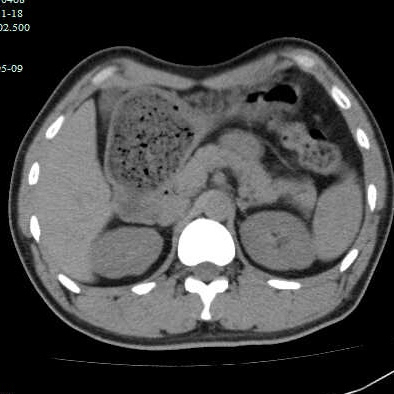

第二个病例,青年男性,也是突然腹痛,症状和第一个类似,首选腹部CT。

因为非影像专业,自己总结肠道植物性结石的特点,混杂密度,多数边缘规则,与正常胃、肠壁结构分界清晰,临床考虑多数急性起病,关键是要问近期是否有大量食用柿子、山楂、黑枣等富含鞣酸食物。